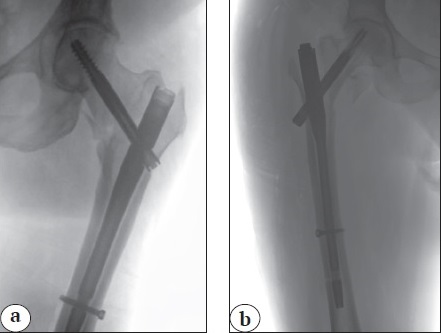

The wedge effect, which develops during nail insertion and leads to the lateralization of the diaphyseal fragment and relative lengthening of the femoral neck, was noted in 10 patients (9.3%) (Figure 1). A pathological medial gap between fragments exceeding 10 mm was observed in 7 (6.5%) patients (Figure 2), and negative medial support was noted in 3 (2.7%) patients (see Figure 1). Significant rotational deformity of the femoral neck with increased anteversion of the head was detected in 3 (2.7%) patients.

Figure 1. Reduction errors in the osteosynthesis of the proximal femoral fractures: a — wedge effect, lateralization of the diaphyseal fragment; b — varus position of the proximal fragment, negative medial support, wedge effect with lateralization of the diaphyseal fragment, incorrect position of the neck screw

Neck lengthening and diaphysis lateralization: a wedge effect

Wedge effect was first described by M.J. O’Malley et al. in 2015 [22]. It manifests as lateral displacement of the femoral diaphysis and is characterized by an increase in varus deformity during intramedullary nail insertion (see Figure 1a). This results in the lengthening of the femoral neck and increased femoral offset, leading to increased load on the implant-bone system in the trochanteric region that raises the risk of fixation failure and neck screw cut-out. Additionally, varus positioning of the femoral neck can lead to poor reduction of medial support and incorrect screw positioning in the head, which can also contribute to mechanical complications.

In our study, we also noted the presence of wedge effect, i.e., varus deformity and femoral neck lengthening. This radiological sign was observed in 10 (9.3%) patients. Therefore, we recommend carefully monitoring lateral displacement during the implantation of the proximal femoral nail and following the recommendations to perform reduction with slight valgus, medializing the nail entry point, and temporarily holding the fragments with pointed bone clamps during nail insertion [23, 29].